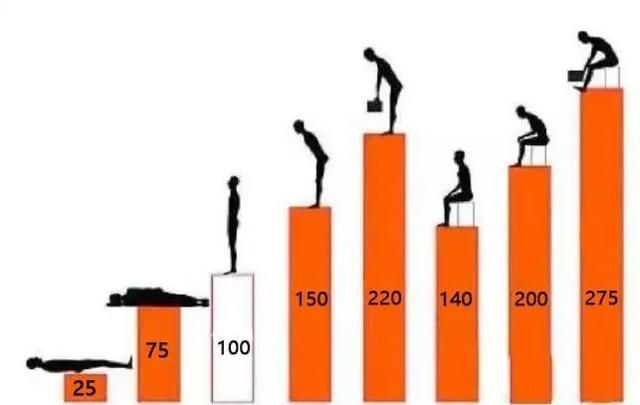

人平躺时,腰椎受力最小,大约25公斤;直立时,腰椎受力约100公斤;坐着时,上半身直立状态下腰椎受力约140公斤。上半身前倾会使腰椎受力骤增,站着身体往前倾时,腰椎受力变为150公斤;坐着身体往前倾时,腰椎受力增大到近200公斤。

不同姿势下腰椎所承受的压力